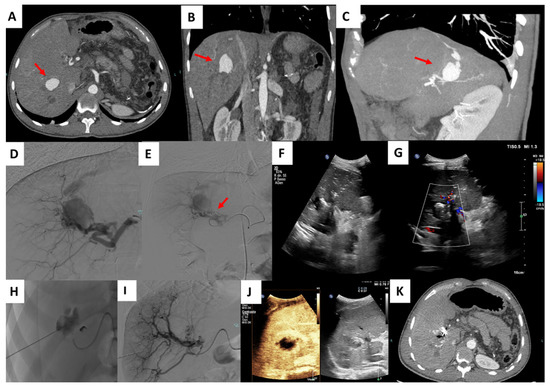

| Patient Sex/Age | Cause | Arterial Territory Involved | PSA mm | Needle, Embolic Agent | Complications |

|---|---|---|---|---|---|

| M 49 | pancreatitis | left gastric a | 20 mm | 22G, glue | asymptomatic splenic migration |

| M 54 | biliary operation | right hepatic a | 21 mm | 22G, glue | no |

| M 25 | TIPS | right hepatic a | 30 mm | 22G, thrombin | no |

| M 22 | biliary operation | right gastric a | 25 mm | 22G, glue | asymptomatic duodenal migration |

| M 58 | surgery | digiunal a | 22 mm | 22G, glue | no |

| F 45 | abdominal abscess | branch of left colic a | 24 mm | 22G, thrombin | no |

| M 38 | abdominal abscess | branch of right colic a | 20 mm | 22G, glue | no |

| F 60 | pancreatitis | left gastric a | 18 mm | 22G, glue | no |

| F 52 | abdominal abscess | right hepatic a | 24 mm | 22G, glue | no |

| M 48 | pancreatitis | gastroepiploic aa | 20 mm | 22G, glue | no |

| M 54 | surgery | dorsal pancreatic a | 23 mm | 22G, glue | no |

| F 28 | trauma | first jejunal a | 22 mm | 22G, glue | asymptomatic migration |

| M 55 | abdominal abscess | branch of the ileocolic a | 20 mm | 22G, glue | no |

| F 49 | abdominal abscess | ileal branches | 18 mm | 22G, thrombin | no |

| F 58 | abdominal abscess | sigmoid branch of IMA | 20 mm | 22G, glue | asymptomatic migration |